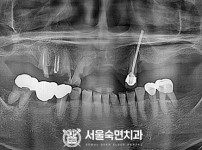

상악동거상술, 뼈이식 / 숙면임플란트 11개 - 포인트임플란트 (이*정님)

해당 게시물은 의료법 제56조에 의거하여 로그인 후 열람이 가능합니다.

구분 임플란트